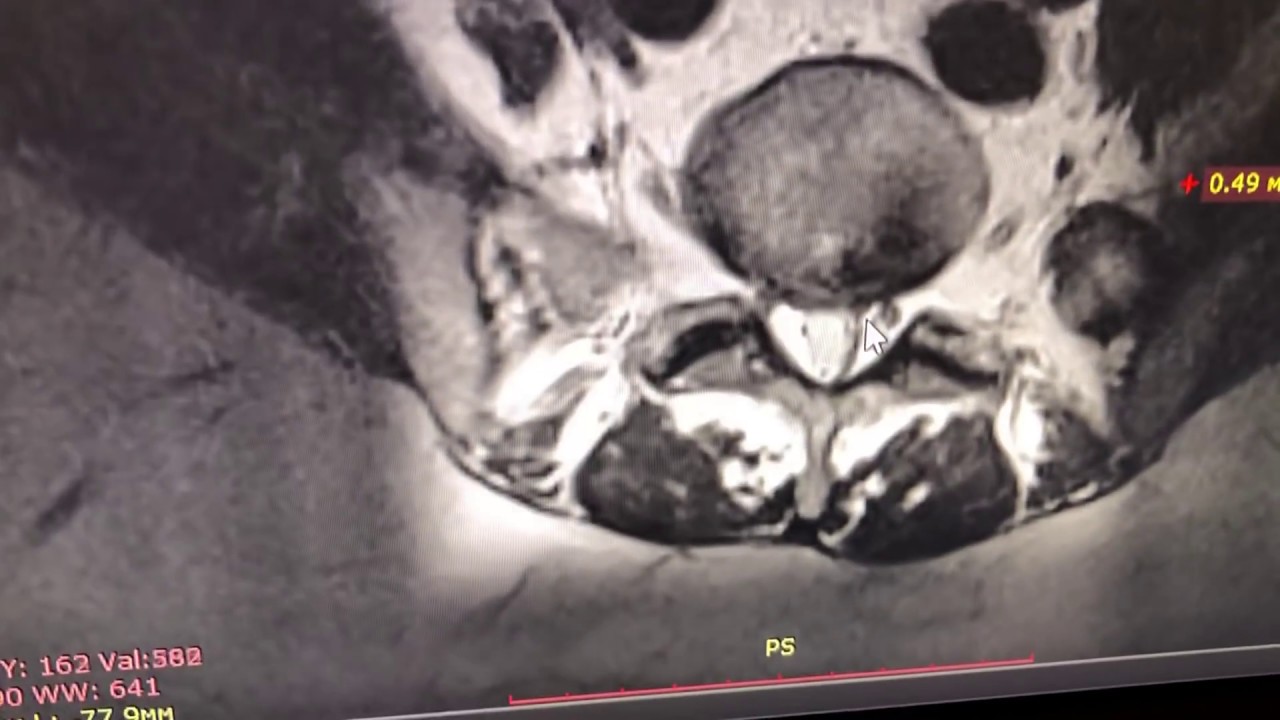

Лучшим методом обнаружить проблему считается МРТ. Но для получения объективных данных, оценки секвестрированной грыжи по размеру и степени влияния на окружающие структуры необходимо выполнение исследования на томографе с напряженностью магнитного поля 1,5 Тл. или выше.

МРТ – это «золотой стандарт» диагностики грыж с секвестрированием, который выявляет участки поражения, локальное воспаление, точное местонахождение секвестра, расположение корешков и спинного мозга. Противопоказанием для проведения данного исследования является наличие в теле металлических (чаще стальных) имплантов и эндопротезов. В этом случае применяют такое исследование, как КТ.